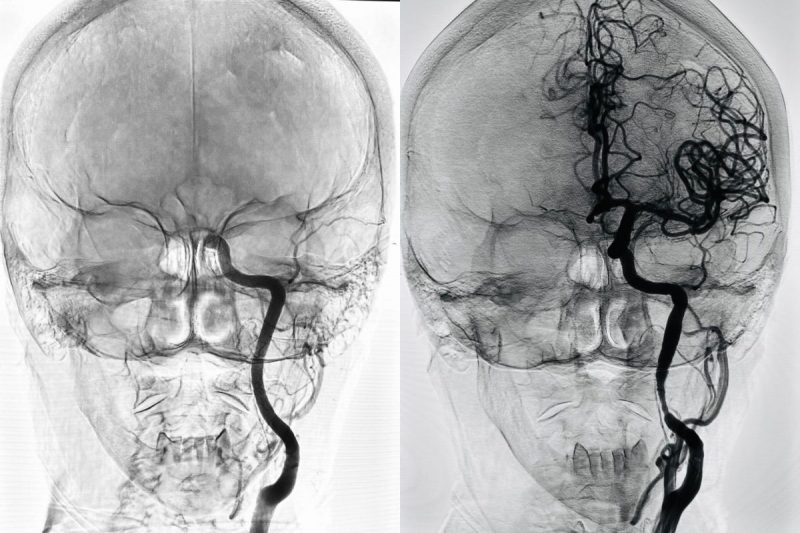

Recurso milionário ajudará pacientes com AVCCérebro acometido por AVC antes e depois do procedimento. Imagem da direita mostra o cérebro sendo irrigado pela corrente sanguínea após trombectomia – Foto: Pedro Magalhães/Reprodução/ND

O Dr. Pedro Magalhães, médico neurologista e neurorradiologista do Hospital São José, explica que o procedimento é um cateterismo que abre a artéria do cérebro, salvando toda a área de uma isquemia.

Para os casos de AVC grave, o procedimento é necessário para garantir uma vida melhor para os pacientes. “Nossa estatística mostra que quando uma pessoa não recebe o tratamento para esse tipo de AVC, menos de 8% volta a uma vida completamente independente”, explica.